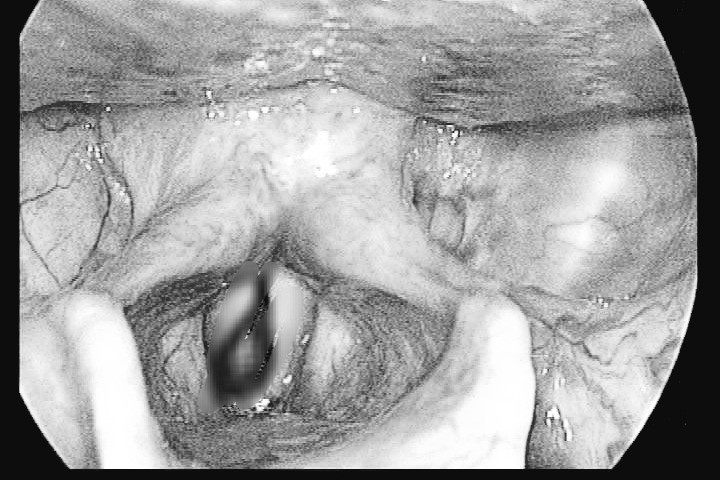

Con đỉa to bằng ngón tay bám chặt cổ họng người đàn ông

Hai tháng nay anh V., 39 tuổi, đau đầu, mệt mỏi, nôn, không ăn được, tự dùng thuốc nhưng không đỡ nên đến viện khám. Bác sĩ phát hiện thanh quản anh có con đỉa no máu, còn sống, bám chặt.